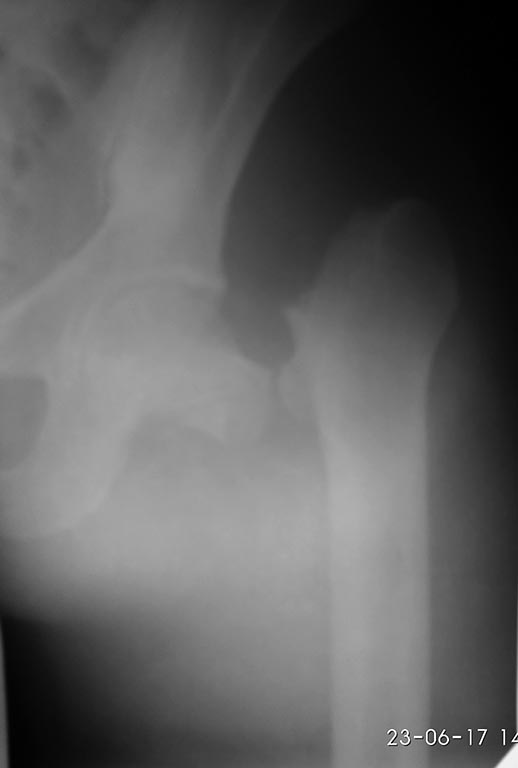

Rt 30 Июнь 2017, 12:58

Пока только фас. Бок технически не получилось (АВФ бедро-голень на уровне колена). Профиль С ЭОПа.

Молодцы, хорошо получилось.

К сожалению угол dhs (140) большой,меньше не возят.